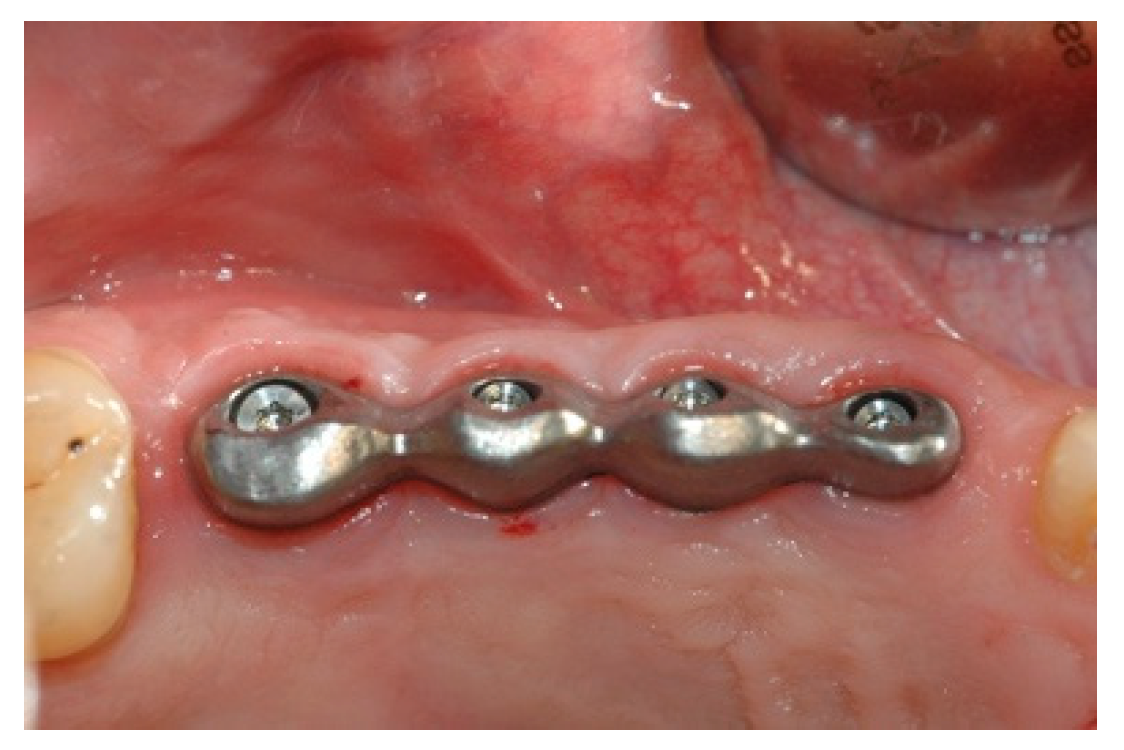

Once the mesostructure was made, it was checked to verify passive adaptation and its precise coupling with the arched fixtures (Figure 8 and Figure 9).

Figure 9. Mesostructure test.

Prosthesis 02 00023 g009